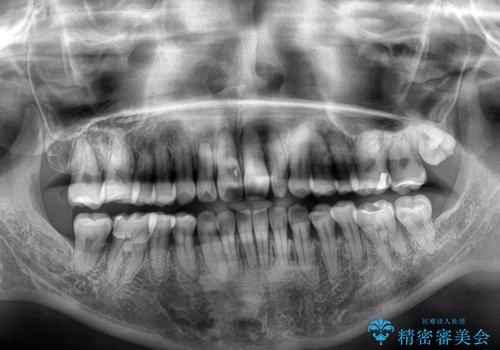

下顎骨が左側にズレて成長してしまったため、左側の咬み合わせが上下反対になっている状態でした。

骨格的なズレは歯列矯正のみでは改善できず、骨切除が必要となります。

そこまでの処置は望んでいらっしゃらなかったため、歯列矯正でのカムフラージュにより咬み合わせを改善することとしました。

予想通り左側の咬み合わせの調整に苦労をしましたが、最終的には違和感のない咬み合わせを達成することができました。